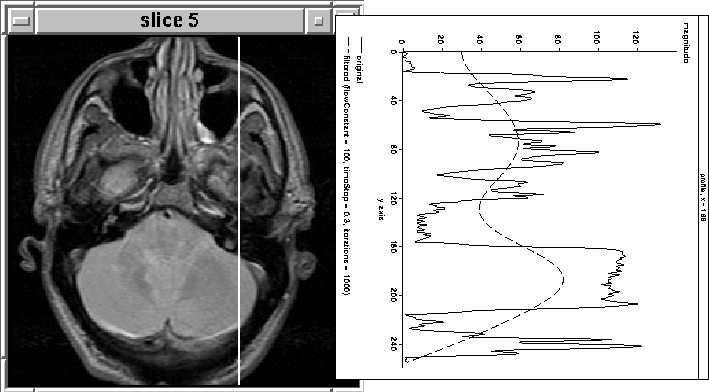

Figure 4.8 shows the results of filtering the 168th column (in 1D) of the fifth PD-weighted slice of MRI Data Set 1 described in Section 8.2. The filter seems to track the brain tissue fairly well.

Figure 4.8: Intracranial boundary detection using 1D nonlinear anisotropic diffusion filtering.

Figures 4.9 and 4.10 show the results of adjusting the number of filter iterations and the flow constant, . In Figure 4.10 the filter precisely tracks the brain tissue while attenuating other tissues. Further, it appears to have produced a profile of the RF inhomogeneity over the brain in the image. Here, the tissues corresponding to brain matter could easily be segmented using a simple threshold.

Figure 4.9: 1D Diffusion. The filter appears to be tracking the data between and . This region corresponds to brain tissue.

Figure 4.10: 1D Diffusion. The filter has precisely tracked the brain tissue. It also appears to have tracked the RF inhomogeneity across the brain.